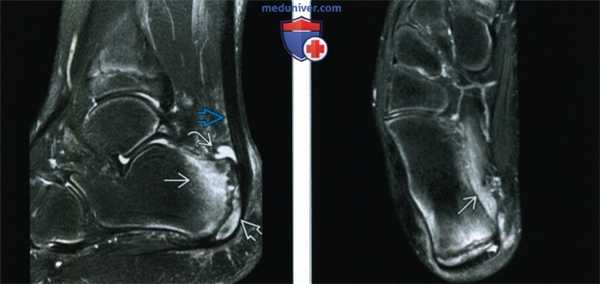

(Левый) У этого же пациента при МРТ в сагиттальной плоскости на Т2ВИ в режиме FS видно, что отек костного мозга захватывает не только буюр пяточной кости, но и апофиз. В синовиальной сумке кпереди от ахиллова сухожилия выявляется жидкость. Также определяются признаки паратендинита ахиллова сухожилия.

(Правый) У этого же пациента при МРТ в аксиальной плоскости на Т2 ВИ в режиме FS, помимо отека костного мозга пяточной кости, визуализируется отек квадратной мышцы подошвы.